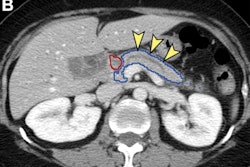

After volumetric segmentation of the pancreas was performed, 88 first-order and gray-level radiomic features were extracted from the CT exams. Ultimately, 34 radiomics features were selected for use by the machine-learning models. The researchers then trained and tested four different classifiers: K-nearest neighbor, support vector machine, random forest, and XGBoost. Two radiologists with nine and three years of post-residency experience, respectively, also evaluated the pancreas in the test set cases on a five-point scale.